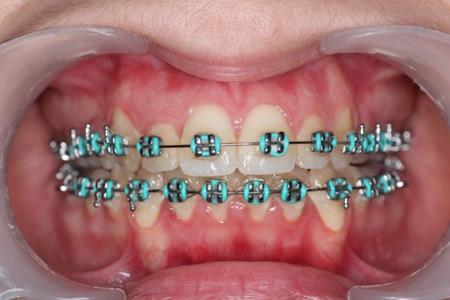

After obtaining the informed consent the orthodontic treatment began and 0,22 Roth straight-wire fixed appliances were bonded. After leveling and aligning, during upper arch expansion, we took impressions and made intermediate study models. We noticed that palatal cusps of the upper premolars could not be intruded by classic mechanics. We decided to intrude first and second bicuspids to resolve the open bite. Skeletal anchorage was indicated and two orthodontic mini-implants were inserted on the palatal side between the premolars.

In this case the implants were loaded after one week with a 100-150 force using an elastic chain.

The intrusion rate obtained was 0,5-1 mm per month without root resorbtion or vitality problems.

Figure 5.Intraoral photography after the mini-implant activation

Intraoral photography after the mini-implant activation